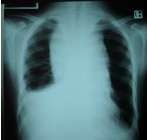

A previously well 14-year-old boy presents to the emergency department with a history of increasing wheeze and shortness of breath over several days. On examination, he has facial fullness and erythema, and his neck veins are easily visible. His chest X-ray is shown below.

A radiologically guided biopsy yields tissue consistent with lymphoblastic lymphoma. Immunocytochemistry is likely to show the cells originate from which lymphocyte group?

A. Mature B cells.

B. Natural killer (NK) cells.

C. Precursor B cells.

D. Reed-Sternberg cells.

E. T cells.

T-cell ALL: obstruction from anterior mediastinal mass (thymus or nodes) – mostly seen in adolescent boys with T-cell ALL (T-cell ALL also has higher leukocyte count), 50-75% Reed-Sternberg cells (Hodgkins)